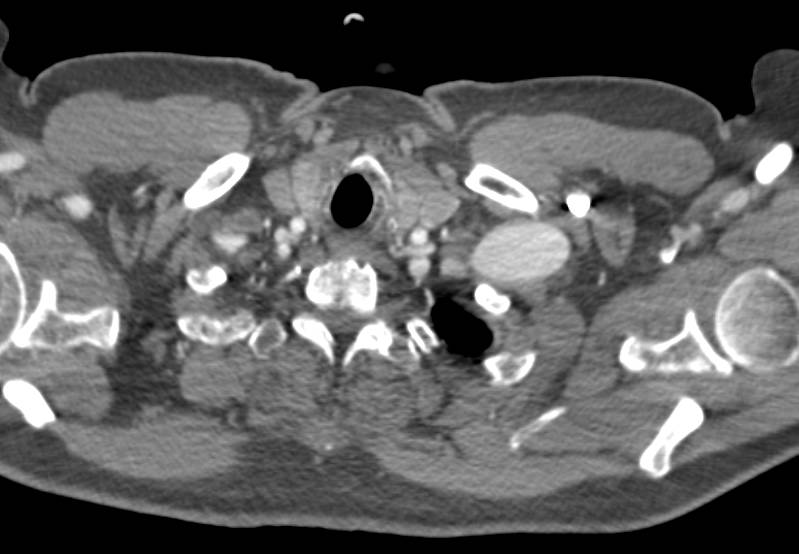

Endovascular Stent in the Abdominal Aorta with Stents in both Renal Arteries